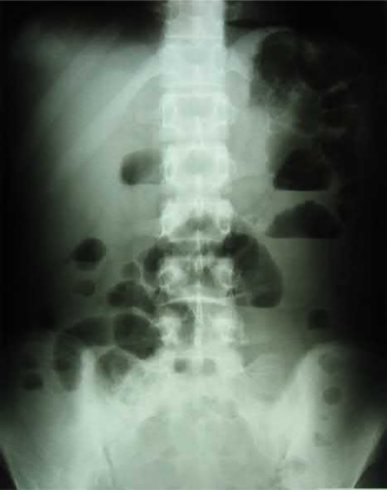

蛋白丢失性肠病:常表现为腹泻,同时伴有严重的水肿、低蛋白血症、尿蛋白较少或无;放射性核素标记的白蛋白经静脉输入后在肠道浓聚显影对诊断有重要价值; 假性肠梗阻:主要以肠梗阻的表现为主,可以出现腹胀腹痛、肠鸣音减弱或消失,腹部平片可见多个气液平面,常合并有肾盂积水,当同时出现有假性肠梗阻及肾盂输尿管积水时对诊断狼疮有颇有价值。